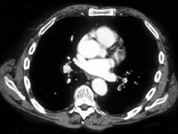

- 单项选择题女性,62岁。突发性胸痛伴咯血、呼吸困难半天。体检: 肥胖,呼吸急促, 左肺呼吸音低。胸部CT如图,应考虑 ( )

D、肺栓塞